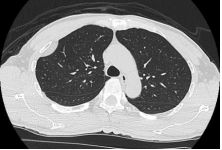

4. 39 y/o female, productive cough for 2 months